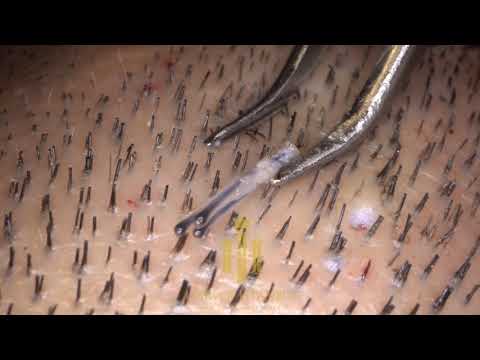

Il metodo alternativo più impiegato è il FUE (estrazione di unità follicolari) che non prevede di asportare un’intera striscia di pelle, ma di rimuovere una per una le unità follicolari da trapiantare. Uno strumento crea una incisione intorno all’unità follicolare, arrivando a una profondità di circa 4 millimetri, in seguito questa viene estratta e poco dopo collocata nella nuova posizione sulla testa (il video è piuttosto esplicito, avvisati).